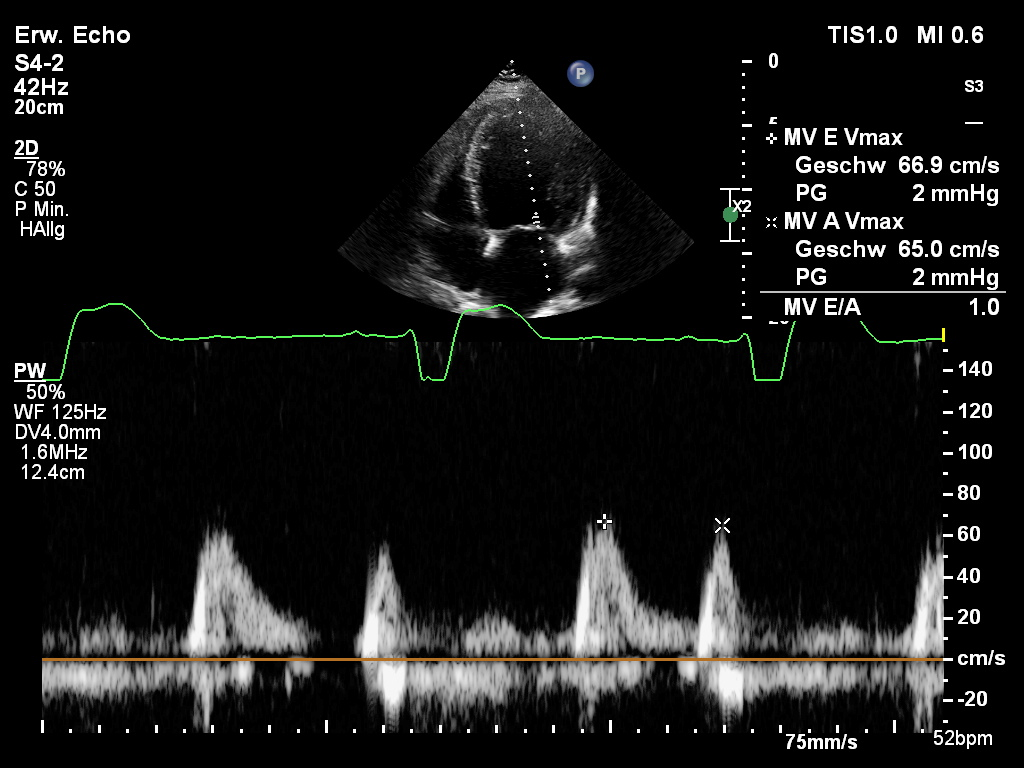

pW-Doppler